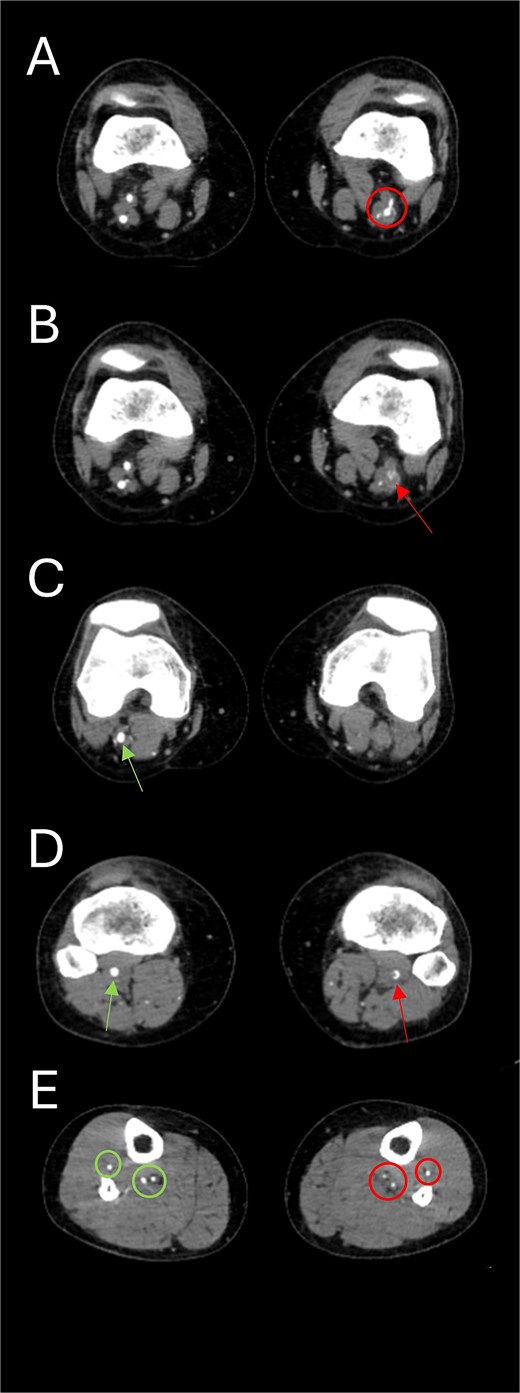

Subsequently, the patient underwent computed tomography angiography (CTA) of the lower extremities which revealed bilateral PSA (Fig. 1). The common femoral arteries trifurcated normally (Fig. 2), but the left superficial femoral artery (SFA) was significantly narrowed (Fig. 3). At the level of the knee, the right SFA joined the PSA to form the popliteal artery (Fig. 4). On the left side, the hypoplastic SFA converged with the PSA more proximally (Fig. 4); however, the artery was occluded, with no clear continuation into the popliteal artery (Fig. 4). Nevertheless, a markedly sub-occluded left popliteal artery was noted at the level of the fibular head, giving rise to a hypoplastic anterior tibial artery and tibio-peroneal trunk (Fig. 4). These findings align with Ahn-Min’s type I bilateral PSA (Fig. 5).

Axial CTA images show (A) the union of the left SFA and SFA; (B) occluded left popliteal artery; (C) the absence of the left popliteal artery and the emergence of the right popliteal artery from the union of right SFA and PSA; (D) the presence of a sub-occluded left popliteal artery (arrow on right leg) at the level of the fibular head and a normal right popliteal artery (arrow on left leg); and (E) the presence of hypoplastic left tibial and peroneal arteries (circles on left leg) along their course in the left leg compared to normal-sized arteries in the right leg (circles on right leg).